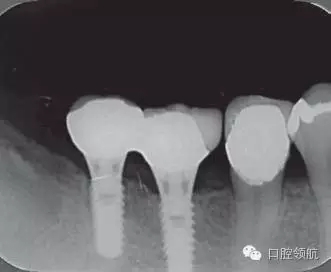

修復(fù)體安裝后的2003年1月復(fù)診時(shí)的X線片上,沒有發(fā)現(xiàn)種植體頸部有骨吸收現(xiàn)象,情況良好(圖2)。但是,2003年8月,因混合陶瓷樹脂部分修復(fù)體的破損而進(jìn)行再制作時(shí),發(fā)現(xiàn)有輕度的咬合疼痛以及舌側(cè)頸部的牙齦有輕壓痛??趦?nèi)沒有觀察到該部位的牙齦紅腫。X線片可以觀察到(左下第6顆牙) 的種植體頸部有達(dá)到第4螺紋的骨吸收現(xiàn)象(圖3)。

圖2 沒有發(fā)現(xiàn)種植體頸部的骨吸收(2003年1月)

圖3(左下第6顆牙)的種植體的骨吸收達(dá)到第4螺紋(2003年8月)